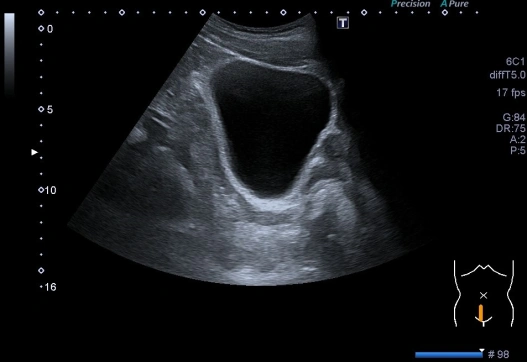

Imágenes anecoicas.

Se forman a partir de estructuras que no reflejan ecos. Se observan en partes del cuerpo totalmente líquidas, como la sangre o la orina. Pueden encontrarse en estructuras no patológicas (vasos sanguíneos, vesícula biliar...) y también en el ámbito patológico como hematomas, bursitis o inflamaciones articulares.